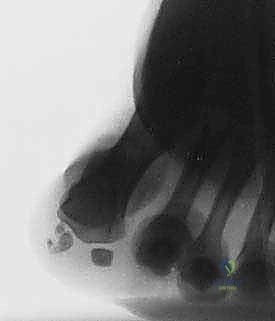

Figure 4: A sesamoid view demonstrating significant fragmentation of the tibial sesamoid, indicative of chronic pathology.

Figure 4: Another sesamoid view highlighting fragmentation.

* Differentiating Bipartite Sesamoid from Fracture: This can be challenging. A fracture line is often sharp and irregular, while a bipartite sesamoid typically has smooth, well-corticated margins. AP radiographs taken in neutral and dorsiflexion can sometimes reveal separation of sesamoid segments in an unstable fracture.